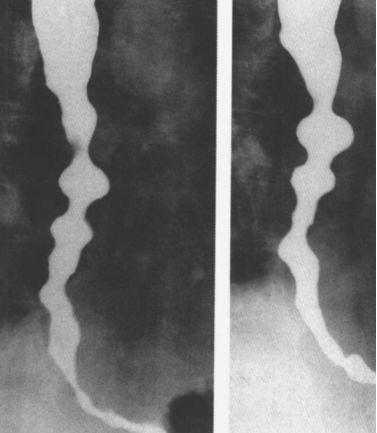

食管静脉曲张esophageal varices食管皱褶呈串珠样,管腔塌陷.

食管重度静脉曲张食管静脉曲张:蚯蚓样,串珠状.

食管下段粘膜皱缝增宽或迂曲,随着静脉曲张进展,病变可延伸到食管中段